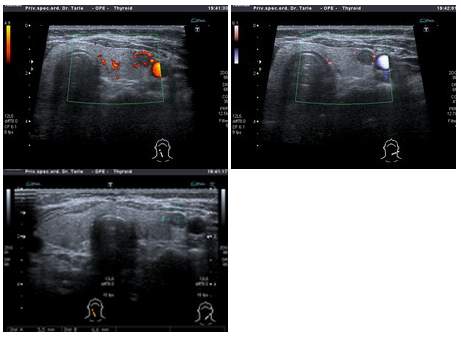

Za dijagnostikovanje bolesti štitnjače koriste se ultrazvuk štitnjače

( najprikladniji bi bio kolor dopler ultrazvuk) , odnosno celog vrata,

zatim laboratorijski krvni testovi za otkrivanje rada štitnjače , ciljana

punkcija štitnjače pod kontrolom ultrazvuka vidljivih čvorova u štitnjači

Ultrazvučnim pregledom štitnjače naročito najnovijim ultrazvučnim kolor

dopler uređajima, moguće je izuzetno dobro prikazati štitnjaču. Pregledom

ultrazvukom može se videti i izmeriti veličina i volumen štitnjače, struktura

štitnjače ( je li homogena-ujednačena tj. uredna ili nehomogena -neujednačena

tj. promenjena struktura štitnjače, odnosno postoje li žarišne tvorevine

u strukturi kao ciste ili čvorovi ). Ultrazvučnim pregledom može se jasno

razabrati radi li se o difuznoj promeni u štitnjači ( cela štitnjača je

strukturalno promenjena) , ali bez žarišnih promena ili je mestimično

promenjena postojanjem žarišnih promena cista, čvorova koji mogu biti

različite veličine, strukture, izgleda na ultrazvučnoj slici.

Ultrazvučnim pregledom kolor doplerom može se kod difuzno promenjenih

štitnjača utvrditi je li prokrvljenost uredna, pojačana ili preslaba.

Ukoliko doktor primeti izuzetno pojačanu prokrvljenost u celoj štitnjači

kolor dopler ultrazvukom , tada uz prisutne simptome pacijenta može s

velikom sigurnošću zaključiti kako se radi o poremećaju rada štitnjače

-koji zovemo HIPERTIREOZA ili pojačani

odnosno ubrzani rad štitnjače. Međutim pravo stanje i konačnu dijagnozu

može se postaviti nakon učinjenih hormona TSH , T3,T4 u krvi.